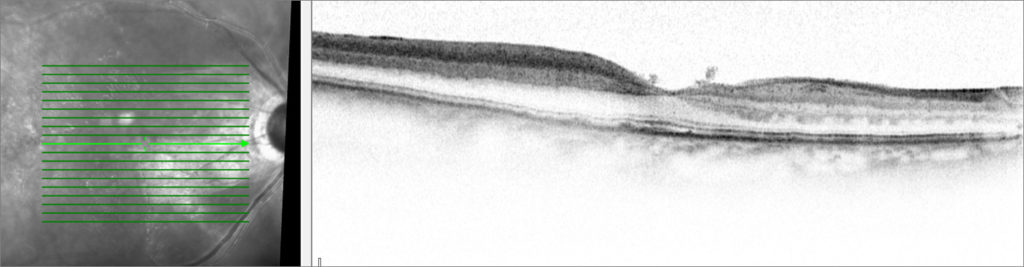

A 80-year-old female experimented nasal visual field loss in her right eye (OD) with preserved temporal visual field. Her past medical history was significant for age-related macular degeneration and hypertension. Best-corrected visual acuity was 6/6 OD and 6/9 OS. A pupillary afferent defect was present OD. Slip lamp examination was unremarkable in both eyes. Fundus examination OD revealed a whitened posterior pole with sparing in the papillomacular bundle. Spectral-domain optical coherence tomography OD revealed inner retinal hyperreflectivity with fovea sparing (Fig 1A). Fluorescein angiography showed a central retinal artery occlusion (CRAO) with cilioretinal sparing OD (Fig 1B).